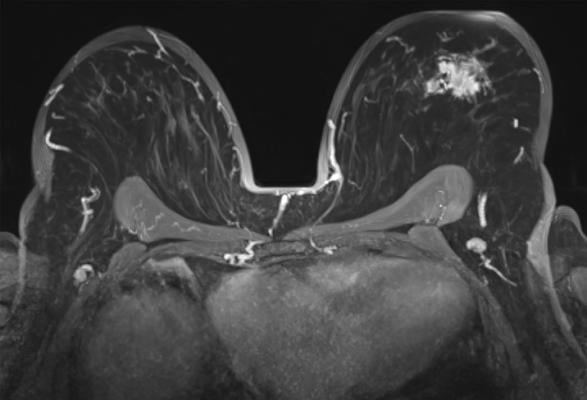

Breast MRI with a tumoral lession in the left breast, axial view. Getty Images

Breast MRI has become the preferred method for imaging women with personal history of breast cancer. Previous studies have shown that breast MRI has a higher cancer detection rate than mammography.

Dr. Lee and colleagues studied the link between second cancer risk and background parenchymal enhancement (BPE) at surveillance breast MRI. BPE refers to the brightening, or enhancement, of background tissue on MRI after administration of a contrast agent. The degree of BPE can vary between and within women. It is thought to be related to changes in the blood supply and permeability of breast tissue, which is affected by hormonal status. Breast cancer treatment in the form of radiation therapy, chemotherapy or endocrine therapy can also alter the BPE in the treated breast.

BPE on contrast-enhanced breast MRI is a known risk factor for breast cancer. Less is known about the links between BPE at surveillance breast MRI and the risk of second breast cancer.